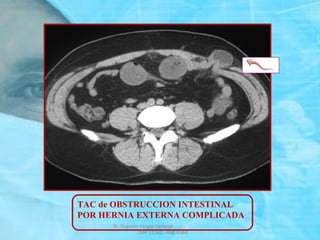

SEGUNDA CAUSA DE OBSTRUCCION DEL INTESTINO

DELGADO. SUCEDE EN HERNIAS COMPLICADAS

CON INCARCELACION o CON ESTRANGULACION.

TAC de OBSTRUCCION INTESTINAL

POR HERNIA EXTERNA COMPLICADA